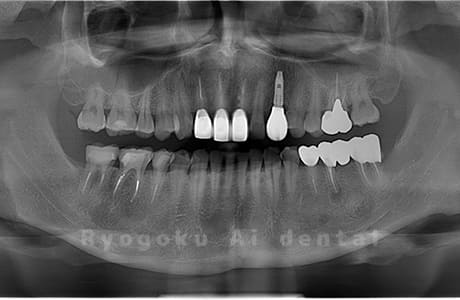

Case14

- 原因

- 重度カリエス、親知らず

- 治療内容

- 親知らずの抜歯、移植手術、マイクロエンド、ダイレクトボンディング

- 治療費用

- 220,000円

他院で親知らずと共に抜歯と診断された患者様です。親知らずの抜歯の必要性と左下奥歯の保存を試みた場合、歯の状態から根管治療、歯周外科、補綴の必要性から、移植治療を選択されました。大きな問題もなく、治療後も経過良好です。

<リスク・副作用>

治療後、痛みや違和感、出血、腫れなどが出る事があります。喫煙者、糖尿病などの方の場合、歯が生着しない場合があります。